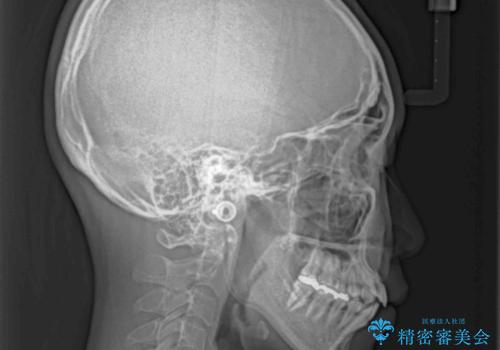

- 前歯のクロスバイトと、口元が閉じにくいとのことで来院された患者様です。

口元の突出感を改善する必要があるため、上下左右の第1小臼歯4本を抜歯し、ワイヤー装置にて矯正治療を行うこととしました。